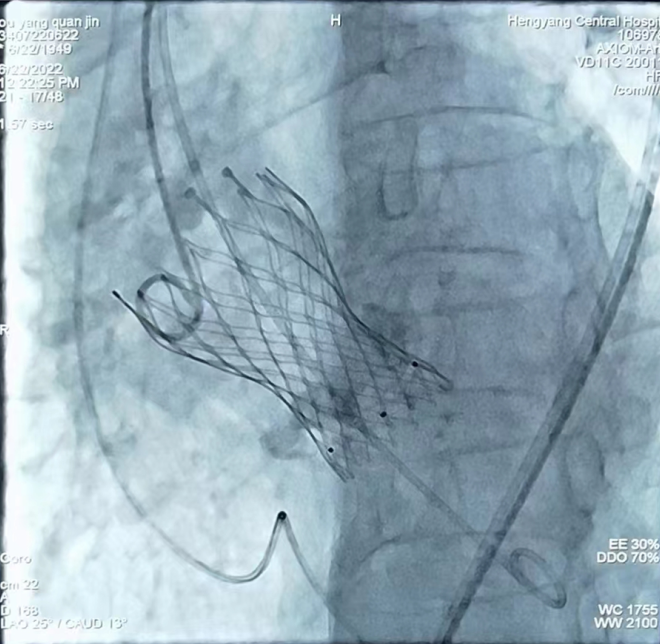

心內一區(qū)通訊員何紅丹報道:為推進結構心臟病介入這一先進技術的開展,我院組建了以心血管內科為主導的TAVR手術團隊,其中包括胸心外科、麻醉科、ICU、手術室、超聲科專家。6月22日上午,我院在心血管內科趙慶禧主任醫(yī)師手術組及TAVR團隊的通力合作下,又成功開展一例TAVR手術,標志著我院TAVR團隊在技術積累、流程優(yōu)化和團隊建設取得重大突破,是我院TAVR技術成熟的一個里程碑。

患者為73歲老年女性患者,心臟彩超示主動脈瓣重度狹窄伴輕中度反流,冠狀動脈CTA示冠狀動脈硬化,主動脈瓣多發(fā)鈣化,右冠狀動脈近、中段管壁鈣化,管腔稍窄。結合患者年齡大、心功能差,不能耐受開胸換瓣等實際情況,趙慶禧主任組織TAVR團隊對患者進行了縝密的術前討論,充分評估了患者主動脈瓣及冠脈的情況,并與患者及家屬進行了充分溝通,經過反復研討,制定了一套精密的手術方案。手術過程歷時3個小時,患者術中術后生命體征平穩(wěn),目前正處于康復階段。

TAVR手術即經導管主動脈瓣置換手術,是一種通過微創(chuàng)介入導管,將人工心臟瓣膜輸送至主動脈瓣區(qū)域并釋放,完成人工瓣膜置入,治療主動脈瓣狹窄的手術。TAVR手術具有創(chuàng)傷小、術后恢復快等優(yōu)點,使得部分以前無法行開胸瓣膜置換的患者成功進行瓣膜置換成為可能。隨著我院TAVR手術團隊臨床經驗的豐富和器械的不斷發(fā)展,TAVR手術在我院越來越成熟,標志著我院的心臟瓣膜置換進入微創(chuàng)時代,為更多的老年、高危、復雜性心臟瓣膜病患者帶來“心”的希望,為衡陽乃至湘南地區(qū)老百姓的健康帶來了福音。